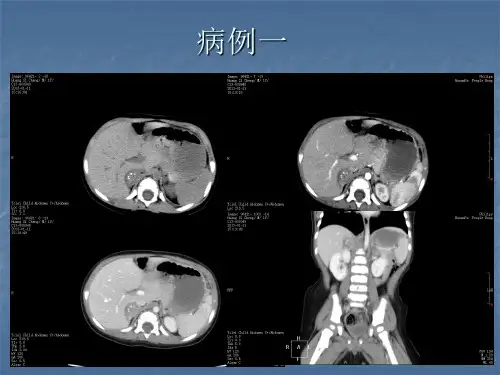

结果25例神经母细胞瘤平扫表现为后腹膜肾上腺区或(和)脊柱前方实性肿块(图1),其中起源于右侧肾上腺16例,左侧9例;17例肿块形态不规则,8例呈类圆形;25例肿块体积均较大,其中16例呈巨大肿块占据大部腹腔;肿块边界清9例,边界不清16例;25例均以实性密度为主,14例肿瘤实质内伴有低密度坏死区,16例发现瘤内钙化,12例钙化形态表现为沙粒样、斑点状、4例钙化呈簇状聚集在肿块中央;5例发现邻近肾脏受侵,其中1例同时合并有肝脏浸润;17例肿块包绕后腹膜大血管生长,其中6例越过中线向对侧延伸(图2);后腹膜淋巴结肿大15例,其中2例合并肝门淋巴结肿大;3例发现远处转移,1例颅底蝶骨大翼骨质破坏(图3),1例双侧髂骨破坏,另有1例同时合并颈部椎旁及脑内双侧额叶、顶枕叶和左侧桥小脑脚多处转移,增强扫描11例肿块呈轻度强化,14例呈中度强化,实质强化程度欠均匀,其中11例中央坏死低密度未见强化;18例发现腹膜大血管周围淋巴结肿大,其中2例合并有肝门淋巴结肿大,增强扫描呈轻-中度强化,程度尚均匀。

结果:儿童肾上腺神经母细胞瘤的CT主要表现有大的不规则肿块25例,密度较均匀18例,钙化12例,囊变或坏死8例,出血4例,越过中线22例,包绕腹膜后大血管20例,腹膜后淋巴结肿大18例,2例肝转移,8例腹腔积液,2例盆腔转移。

肿块不均匀强化,肾脏向后外侧移位24例,肾脏轮廓完整。

2.2 CT表现

肾上腺神经母细胞瘤单侧发生,位于腹膜后肾上腺区。

肿块

直径2.5 cm~13.0 cm,形态不规则,边缘呈结节状20例,密度较均匀18例,钙化12例,囊变8例,出血4例。

越过中线向对侧延伸22例,包绕腹膜后大血管20例,腹膜后淋巴结肿大18例,2例肝转移,8例腹腔积液,2例盆腔转移。

CT增强扫描示肿块不均匀强化,肾脏向后外侧移位24例,肾脏轮廓完整,无明显破坏20例,受浸润4例,肾积水3例。

3.2 儿童肾上腺神经母细胞瘤的CT诊断要点

肾上腺神经母细胞瘤平扫示大的不规则肿块,无明确包囊,呈浸润生长,新生儿期肿瘤易出血、坏死或囊变。

常有点状钙化,肿块常向跨越中线向对侧延伸,包绕腹膜后大血管,或侵入椎管内或肝脏。

增强扫描肿块不均匀强化,肾脏轮廓完整,大多被肿瘤压迫向后外侧移位,少数肾脏受浸润,并可发生肾积水。